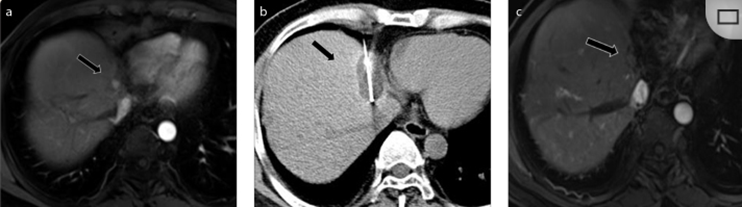

79 歲男性,肝轉(zhuǎn)移(結(jié)直腸癌)腫瘤的完全消融病例

( a ) 軸向 MRI 和 ( b ) 軸向 CT 顯示肝S8段有一個16mm的病灶,鄰近肝緣。( c )冷凍消融期間CT顯示放置了2個冷凍探針,低密度冰球包圍病灶。(d)術(shù)后1個月隨訪 CT顯示冰球?qū)?yīng)的壞死區(qū)域,未見復(fù)發(fā)。(e)術(shù)后6個月的CT,壞死區(qū)域縮小,未見復(fù)發(fā)。(f)與基線影像(g)相比,12個月后的FDG-PET/CT顯示未見FDG攝取。

62歲女性,肝轉(zhuǎn)移(卵巢癌)腫瘤的完全消融病例(a)軸向CT顯示病變位置毗鄰心臟和上腔靜脈(黑色箭頭)。(b)術(shù)中軸向CT掃描:使用三個冷凍探針。1個月后的軸向(e)和冠狀位(f)增強CT掃描顯示低密度區(qū)域,由于肉芽組織反應(yīng)引起的邊緣增強。

技術(shù)成功100%,92% 的病灶中觀察到腫瘤完全消融。16 名患者 (33%) 出現(xiàn)局部復(fù)發(fā)。10 名患者 (20%) 因局部復(fù)發(fā)或腫瘤消融不完全而接受二次冷凍消融術(shù)。

7名患者出現(xiàn)輕微并發(fā)癥,未發(fā)現(xiàn)膿腫形成、膽漏、膽汁瘤或血液學(xué)變化。冷凍消融可安全、有效治療毗鄰重要臟器的原發(fā)性肝臟腫瘤和肝轉(zhuǎn)移瘤患者,有效控制腫瘤局部進展,使患者生存獲益。我國作為肝癌大國,對于肝癌的治療一直給予高度重視。基于專家共識和相關(guān)文獻研究結(jié)果顯示,冷凍消融技術(shù)具有高效、低成本、創(chuàng)傷小、適應(yīng)證廣、并發(fā)癥相對較少等優(yōu)點,可有效延長患者生存期、提高生活質(zhì)量、降低患者經(jīng)濟負擔(dān)。因此,冷凍消融技術(shù)在肝癌的應(yīng)用中有著極高的潛力和廣泛的發(fā)展空間。